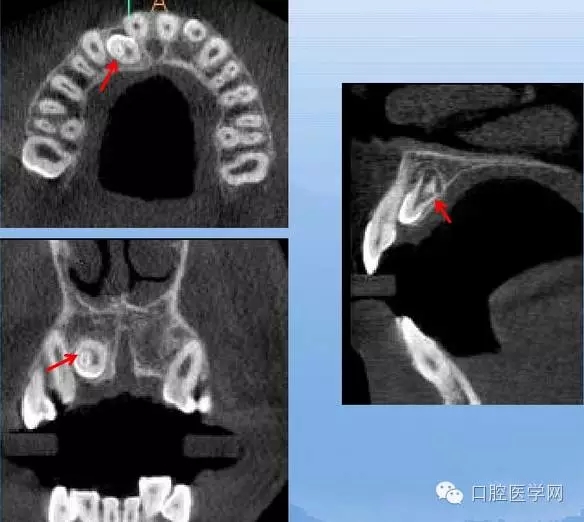

額外牙

X線表現(xiàn):最多見于上頜兩中切牙之間;圓錐形,根短小;拍攝X線片可確定額外牙的數(shù)目、位置、形態(tài)與鄰牙的關(guān)系。